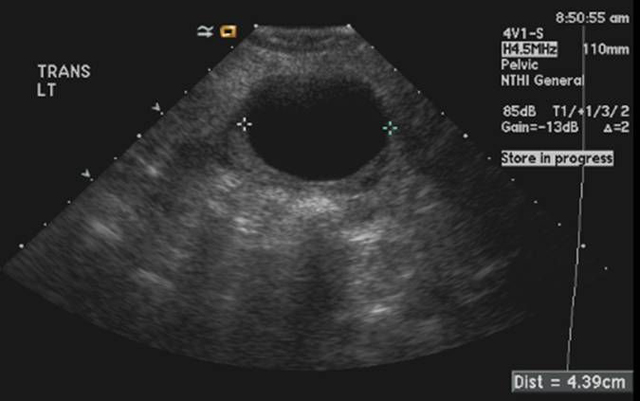

Simple ovarian cyst

Ultrasound

Calipers demarcate a 4.3 cm fluid-filled cyst arising from the left ovary which demonstrates the features of a simple cyst: anechoic, or completely black echotexture; thin, imperceptible wall; and posterior acoustic shadowing in which the tissues posterior to the cyst are more echogenic, or whiter, than the surrounding tissue.